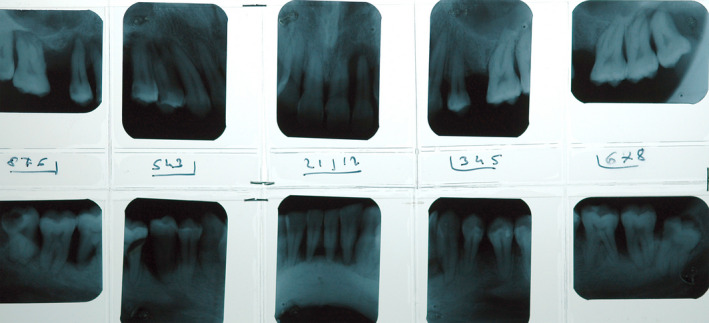

FIGURE 2.

Radiographic full status of the patient in Figure 1 showing severe bone loss with multiple angular intrabony defects

The deeper inhalation and prolonged contact and absorption time associated with cannabis smoking suggests that it may contribute to the etiology of periodontal disease (Figures 1 and 2).